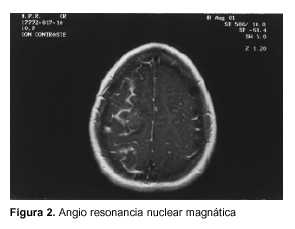

Se solicitó además angio resonancia nuclear magnética (figuras 1 y 2).

Para la realización de la misma se le administró contraste intravenoso, sin tener en cuenta los antecedentes previos inmediatos de atopía. Ello provocó nuevamente un cuadro anafiláctico que requirió tratamiento con antihistamínicos (clorfeniramina) y hemisucccinato de hidrocortisona por vía intravenosa durante cinco días.

Al segundo día de evolución instala en forma aguda una monoplejia braquial izquierda, constatándose en la tomografía de cráneo una imagen hipodensa compatible con un infarto fronto-parietal derecho. Es de destacar que esta complicación surge cuando los parámetros de la coagulación se habían normalizado completamente.